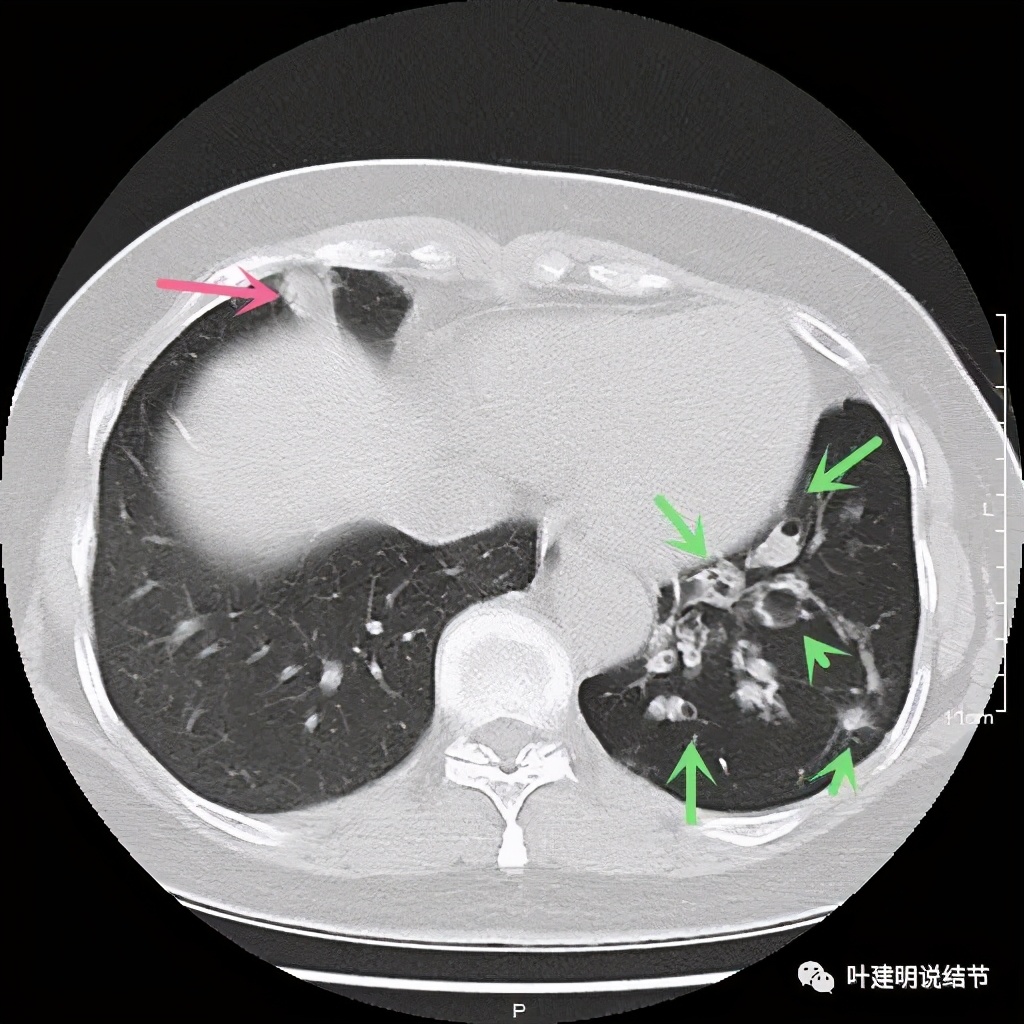

其实若从以上影像上看,恶性还真不能除外的,相对来说,恶性的可能应该大于良性。但看肺结节,我们在看细节特征的同时,还要看其他肺野有没有异常,综合来考虑。因为她的左下肺其他部位有病变存在,先来看下图像:

左下肺野多发支气管扩张呈囊状,也有一些实性密度的结节(考虑扩张支气管内的痰栓)。右侧也有实性炎性病灶。所以综合来看,左下之前的结节也得考虑与这些同源,一个原因来解释更为合理,所以恶性的可能性又小了。我建议其随访视察。昨天来复查,我们来看下这次的CT图像: